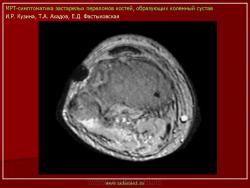

Магнитнорезонансная томография в диагностике повреждений костей голеностопного сустава.

Семиотика стресс-переломов аналогична скрытым переломам костей голеностопного сустава и стопы. Дополнительно визуализируется периостальная реакция. Однако в отличие от скрытых переломов патологические изменения визуализируются и рентгенологически.

При проведении МРТ больным с переломами костей голеностопного сустава и стопы не ставится задача оценки переломов. Изучается состояние сухожильно-связочного аппарата и параартикулярных мягких тканей. Гипсовые повязки не оказывают существенного влияния на качество и информативность изображений.